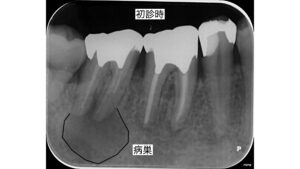

右下奥歯の根の病気に対する精密根管治療

•診査診断:CTで大きな根尖病変を確認しました。さらに詳しく調べると、前回の根管治療で適切な治療ができていないことがわかりました。通常は、根の先端まで充填剤(ガッタパーチャ)が詰めるべきはずがなされていない状態でした。

そのため、根管内に隙間が存在し、隙間に感染源が残存しており病気が発症した可能性があると考えられます。

術後のレントゲンやCT画像でも病変(透過蔵)が縮小、改善されていることが確認できました。